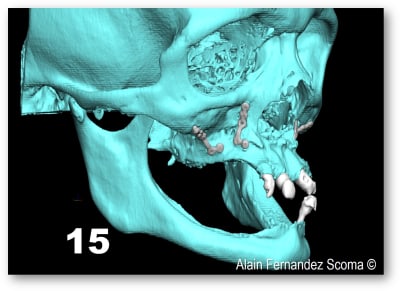

Olieve, un autre cas, patient de 24 ans maladie génétique entrai ant la perte de l'os médullaire, agénésie multiples ayant bénéficié d'un Leffort 1. Selon les critères que tu indiquais précédemment une MCI serait contre indiquée ?

voici ce qui a été fait par un chirurgien maxillo en AG qui avait à son actif une vingtaine d'implants posés, la S.I.A.O (17), pose des guides à appuis osseux (18, 19), résultat fin de chirurgie (20).